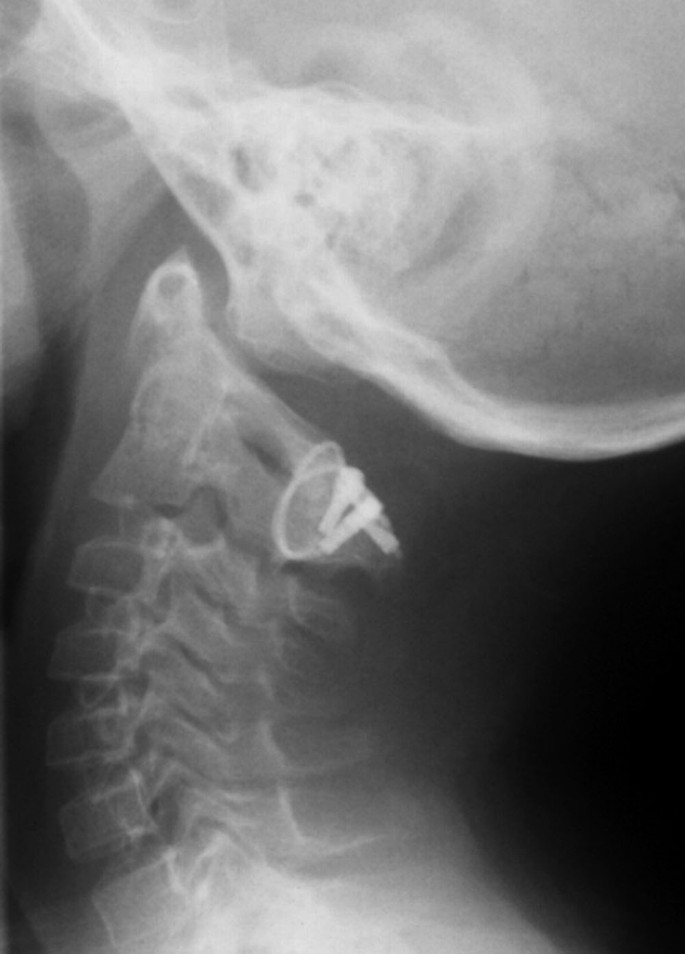

Meestal is maar één facetgewricht aangedaan waardoor de pijn zich ook maar aan één zijde van de achterkant van de nek bevindt. Bij iedere comateuze of gesedeerde patiënt bij vermoeden van craniale letsels verwardheid agitatie verminderd bewustzijn en bij patiënten met nekpijn of neurologische uitval is de immobilisatie van hoofd en nek ter plaatse bij resuscitatie en bij transport zeer belangrijk. Yellow dotted line indicates ICM. PDF Renewing the Dutch guideline for medical specialists. Scale bar 250 μm. De belangrijkste oorzaak van een ernstige complicatie zoals het Vertebro-Basilaire Infarct VBI na behandeling van cervicale hoofdpijn is de Vertebro-basilaire Arteriële Dissectie VAD.

Naast de VAD bestaat ook de Internal arotid Artery Dissection _ ICAD. B Representative IF images showing hEPSCs differentiated into HYP-like cells within host monkey embryos at dpf9. Facetgewrichten kunnen net als andere. Deze prothese is technisch zo geconstrueerd dat ze de functie van de verwijderde tussenwervelschijf zoveel mogelijk overneemt en vermindering van de buigzaamheid van de. Yellow dotted line indicates ICM. Arrow indicates a TD-positive hEPSC expressing GATA4.